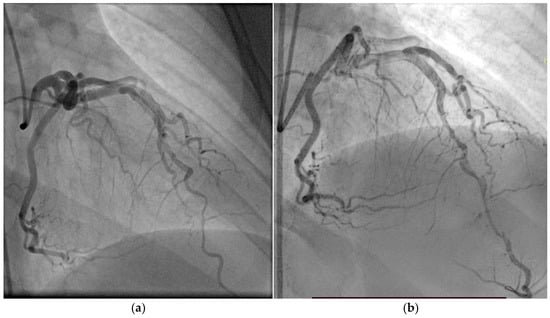

3.3. Case 3